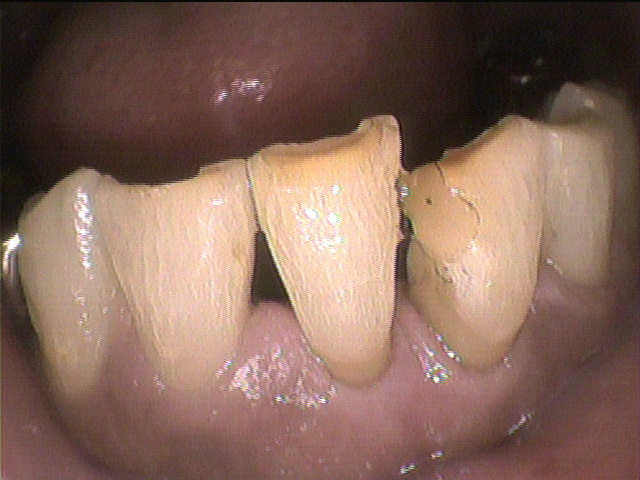

クリーニング前

数年ぶりにクリーニングにいらした患者さんです。

タバコやコーヒーによる着色、歯石、プラークがべったりと付着していました。

1回では取り切れないため、2回に分けてクリーニングを行うことになり

特に汚れが目立っていた下の前歯を中心に、できる限り除去しました。